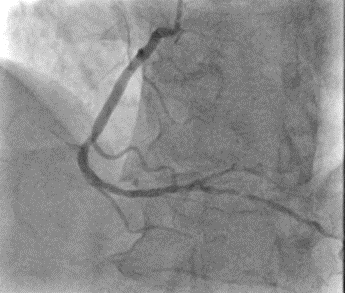

Angiogram

•Left Main Coronary Artery: Patient with minor non critical atheroma

•Left Anterior Descending Coronary Artery: Patient with minor non critical atheroma

•Circumflex Coronary Artery: Co-dominant artery – patent with minor non critical atheroma

•Left Ventricle: EDP 10mmHg, no significant aortic pullback gradient

•Right Coronary Artery: Co – dominant artery, right PDA is a moderate vessel with severe 80% mid vessel stenosis